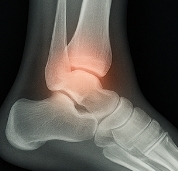

발목 접질렀을때 가능한 치료 방법

발목 접질렀을때 치료는 손상 정도에 따라 다릅니다.

- 경미한 경우: 냉찜질, 안정, 물리치료.

- 중등도 손상: 석고 고정, 보조기 착용, 약물치료.

- 심한 손상: 인대 파열 시 수술적 치료 필요.

발목 접질렀을때는 반드시 전문가의 정확한 진단을 받아야 합니다.